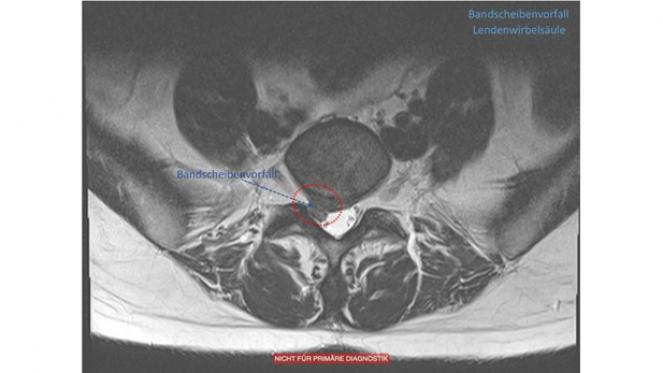

Bandscheibenvorfälle (NPP)

Bandscheiben sind flexible, faserknorpelige Verbindung, die als Stoßdämpfer zwischen den Wirbel dienen.

Mit zunehmendem Lebensalter kann es zu verschleißbedingten Rissen am äußeren Ring der Bandscheibe (Faserring) und zu einem Austritt des gallertartigen Kerns kommen. Dieser kann die benachbarten Nervenwurzeln oder das Rückenmark zusammendrücken und zu lokalen oder ausstrahlenden Schmerzen in den Armen und Beinen, ggf. auch mit Sensibilitätsstörungen und motorischen Ausfällen, führen.